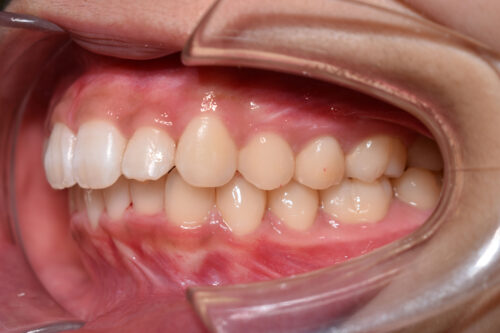

初診時年齢14歳女性

歯のがたつき(叢生)と

出っ歯

を気になさり

巣鴨 ・ 池袋よりひとつ隣駅の東京都豊島区大塚駅すぐの大塚たまみ矯正歯科へ

来院されました。

過蓋咬合: 下の歯が深く噛みこみ

また

ANGLE 2級 : 上顎前突傾向で

出っ歯を呈していました。

ワイヤー矯正治療7か月後です。